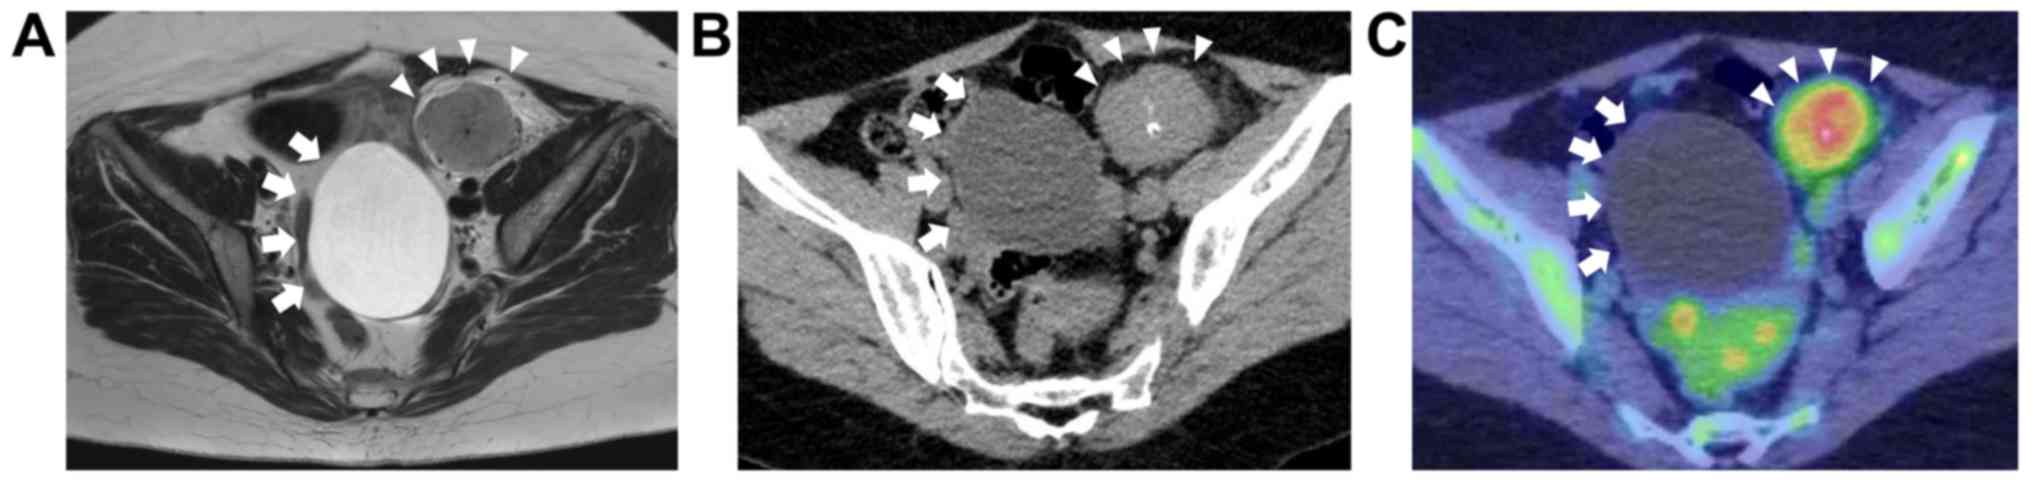

A 47-year-old gravida 5, para 3 female was referred to our hospital because of a pelvic mass accidentally found by radiological examination at a health checkup. She had no systemic symptoms such as pelvic pain, fatigue, fever, or weight loss. Transvaginal ultrasound examination revealed a 7.8 cm-sized simple cystic tumor on the left ovary. Magnetic resonance imaging (MRI) revealed an 8.2 cm-sized ovarian cyst and a 5.2 cm-sized heterogeneously hyper-enhanced solid tumor in the retroperitoneal space of the left pelvis on T2-weighted (T2W) images (Fig. 1A). On T1-weighted (T1W) images, the pelvic retroperitoneal tumor was homogeneous and nearly isointense to uterus in signal intensity. Computed tomography (CT) revealed partial calcification of both the cystic and solid pelvic retroperitoneal tumors, with no pelvic lymph node swelling (Fig. 1B). 18F-fluoro-2-deoxy-D-glucose positron emission tomography combined with computed tomography (FDG-PET/CT) detected high radiotracer uptake by the retroperitoneal tumor [maximum standardized uptake value (SUVmax): 4.14], with no distant metastases (Fig. 1C). Serum levels of carcinoembryonic antigen (CEA), cancer antigen (CA) 19-9, CA125, and interleukin 6 (IL-6) were within the normal range. Except for the above-mentioned findings, serum biochemical and clotting studies were within the normal limits.

Figure 1.

Radiological findings of pelvic retroperitoneal Castleman's disease. Arrowheads indicate retroperitoneal tumor. Arrows indicate ovarian cyst. (A) T2-weighted magnetic resonance imaging findings. (B) Computed tomography findings. (C) 18F-fluoro-2-deoxy-D-glucose positron emission tomography combined with computed tomography findings.